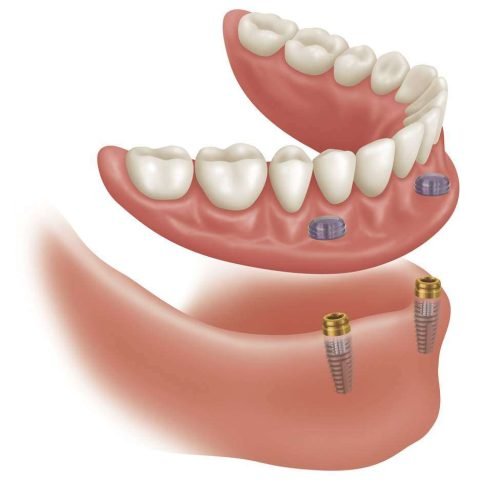

La sobredentadura Locator ® es una prótesis dental removible que se retiene por implantes dentales y se soporta por la mucosa oral. (implantomucosoportada).

A diferencia de las prótesis tradicionales, esta se fija a los implantes mediante unos pilares llamados aditamentos o attachments, que proporcionan una retención mucho más segura y estable. Esto te permite realizar una masticación más eficiente y una mejor estética.

El sistema de fijación Locator consiste en un pilar (macho) que se atornilla al implante, el cual recibe un inserto o goma de retención (hembra) que va adherido a la prótesis.

Existen 2 gamas de insertos para distintas angulaciones de implantes y cada color de goma presenta una fuerza de retención distinta, dependiendo de cada caso.